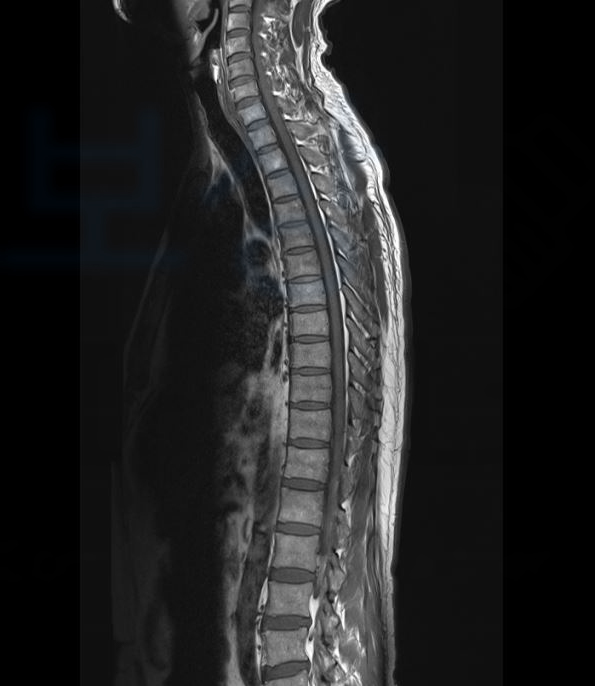

이때 일반 보험 소비자는 보험사에 대응할 경험이나 정보가 없기 때문에 속수무책으로 당할 수밖에 없는 입장이죠. 보상 파트너가 처리했던 보상 사례 소개해드리겠습니다. 현장에서 일하던 중 무거운 물체가 등뼈에 떨어지는 사고를 당한 고@@님, 극심한 통증을 호소하며 Mri 촬영 등의 정밀 검사를 시행하셨는데요, 검사 결과 고@@님은

image

S22090 흉추골절, 폐쇄성 진단받으셨고 최소 10주간의 허리 보조기 착용하며 보존적 치료를 하셔야 했습니다. 고@@님은 내 보험에서 청구할 수 있는 실비, 입원비, 골절 진단비를 이미 보상받으셨고 주변 지인으로부터 소개받아 보상 파트너로 연락 주시게 되었습니다.